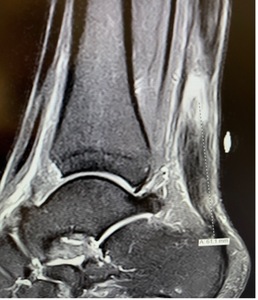

Six months after surgery, the patient demonstrated excellent range of motion and the ability to do a double leg hop (see Video 2). At 6-months, post-operative MRI showed the tendon defect to be almost completely filled with new tissue that was well-integrated with the underlying tendon (Figure 6).

This patient presented a challenge due to the chronic nature of the tear and the large defect with cavitation. It was determined that the repair should be surgically augmented. The goal of this repair was to induce rapid host tissue ingrowth and provide load sharing strength to improve overall tendon healing via use of the BioBrace implant. Six-month post-operative imaging indicated that the defect was infiltrated with new tissue and that the BioBrace implant was integrated with surrounding host tissue. Post-operative functional tests suggest that the patient is on track towards an excellent recovery with dorsiflexion and plantar flexion strength and motion scores greatly improved compared to preoperative values. At six months post-op, the patient was back to full duty, loading and unloading heavy cargo and getting into and out of an 18-wheeler truck. As this was a worker’s compensation injury, early return was even more impressive after repair of a chronic Achilles tendon rupture. While this case report is promising, studies with more patients and longer-term follow-up are required to further evaluate the potential clinical benefits of this implant.